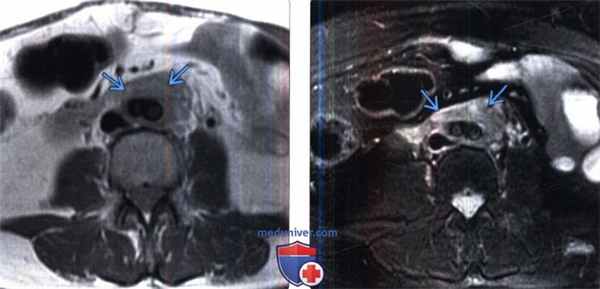

(Слева) МРТ, Т1-ВИ, аксиальная проекция: выявлен слой соединительной ткани , окружающей переднюю и боковую поверхности бифуркации подвздошных сосудов. Мягкая ткань имеет низкую и умеренную ИС.

(Справа) МРТ, Т1-ВИ, режим подавления сигнала от жировой ткани, аксиальная проекция: у этого же пациента выявлено мягкотканное образование с высокой ИС, которое окружает бифуркацию подвздошных сосудов, что соответствует активному фиброзу.